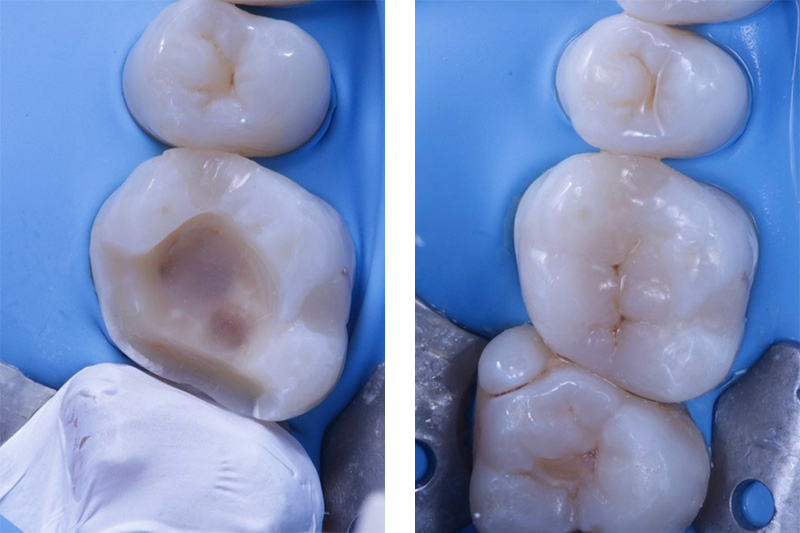

Nel ripristino della morfologia e della funzionalità dell’elemento danneggiato si utilizzano materiali altamente estetici che si mimetizzano perfettamente con il dente sano e dalle caratteristiche meccaniche eccellenti.

Nel caso in cui la perdita di tessuto dentario sia così estesa, per cui un’otturazione non sarebbe in grado di garantire la corretta forma e la sufficiente resistenza, presso lo Stomatologico Agrate utilizziamo ampiamente gli intarsi.

In questi casi, dopo aver rilevato un’impronta digitale 3D, la parte mancante dell’elemento dentario viene realizzata in laboratorio con tecniche digitali cad-cam, rifinita a mano per garantire assoluta precisione ed estetica e solo successivamente cementata in bocca. Tutto ciò permette di raggiungere standard di estetica e di resistenza del restauro eccellenti.